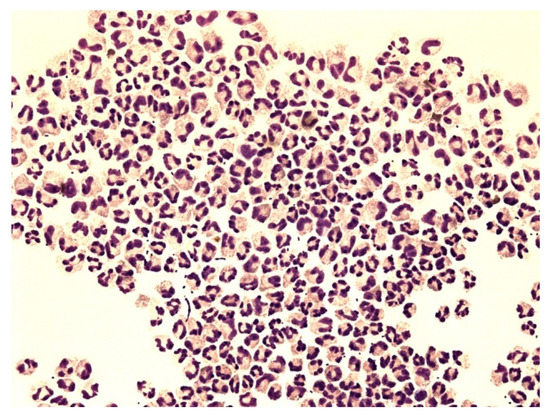

Figure 8.

Predominance of neutrophils in pleural effusion; KEB = 32.5; non-purulent reaction in the pleural cavity of patients with atopic bronchial asthma.